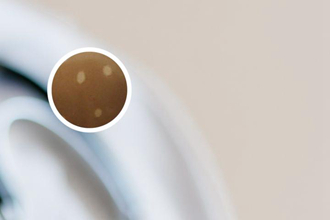

毛囊周圍色素殘留是指在白癜風(fēng)患者皮損周圍,由于毛囊中的色素沉積導(dǎo)致的色素沉淀現(xiàn)象。這是由于白癜風(fēng)患者皮膚色素細(xì)胞的功能障礙,使得周圍的色素沉積在毛囊周圍,造成了殘留色素。

皮損周圍顏色稍加深是指在白癜風(fēng)患者皮損周圍,皮膚顏色相對(duì)于正常皮膚稍微加深。這可能是由于患者的黑色素細(xì)胞在皮損邊緣重新分布,導(dǎo)致了顏色的略微加深。

毛囊周圍色素殘留是因?yàn)橹車】灯つw的黑色素對(duì)比增加。

皮損周圍顏色稍加深是黑色素的重新產(chǎn)生的結(jié)果。